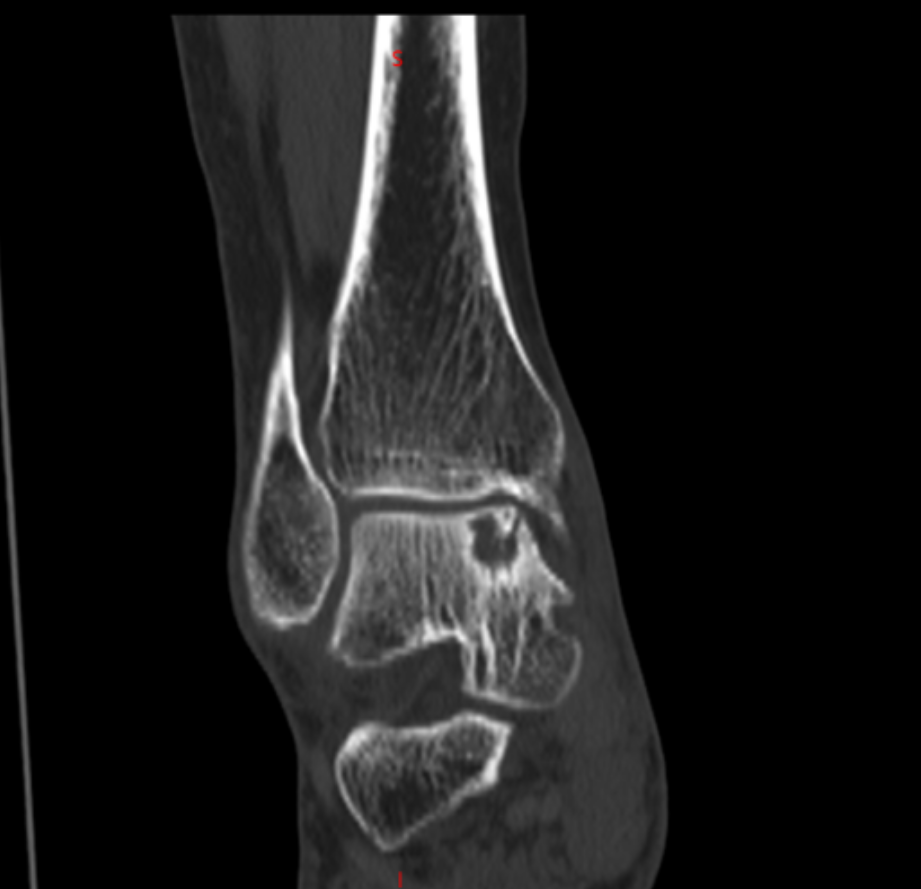

北京积水潭医院郑州医院、郑州大学附属郑州中心医院足踝外科李恒的诊室,李恒指着片子解释距骨内侧出现囊性变,这确实是棘手的问题。由于内部压力大,不但会疼痛,还有可能引起距骨塌陷骨折。我抢答:能不能不换踝关节?我还年轻,而且换踝关节费用太高了。

踝上截骨治疗踝关节关节病及距骨骨软骨损伤的手术治疗,对医生手术技术要求高,需要对踝足部的力线及平衡调整有丰富临床经验,术中要有很强应变能力。在李恒和足踝外科小组配合下顺利完成!

术后复查X线,非常完美。李恒提醒,踝关节是人体中负重最大的关节,出现问题会给生活带来极大的痛苦和不便,崴脚并非小事,若早期处理不当,错过最佳治疗时机,轻则遗留慢性疼痛,重则导致创伤性关节炎、慢性踝关节不稳等后遗症,所以“走路看路”+“积极的运动锻炼”,预防踝关节损伤非常重要!